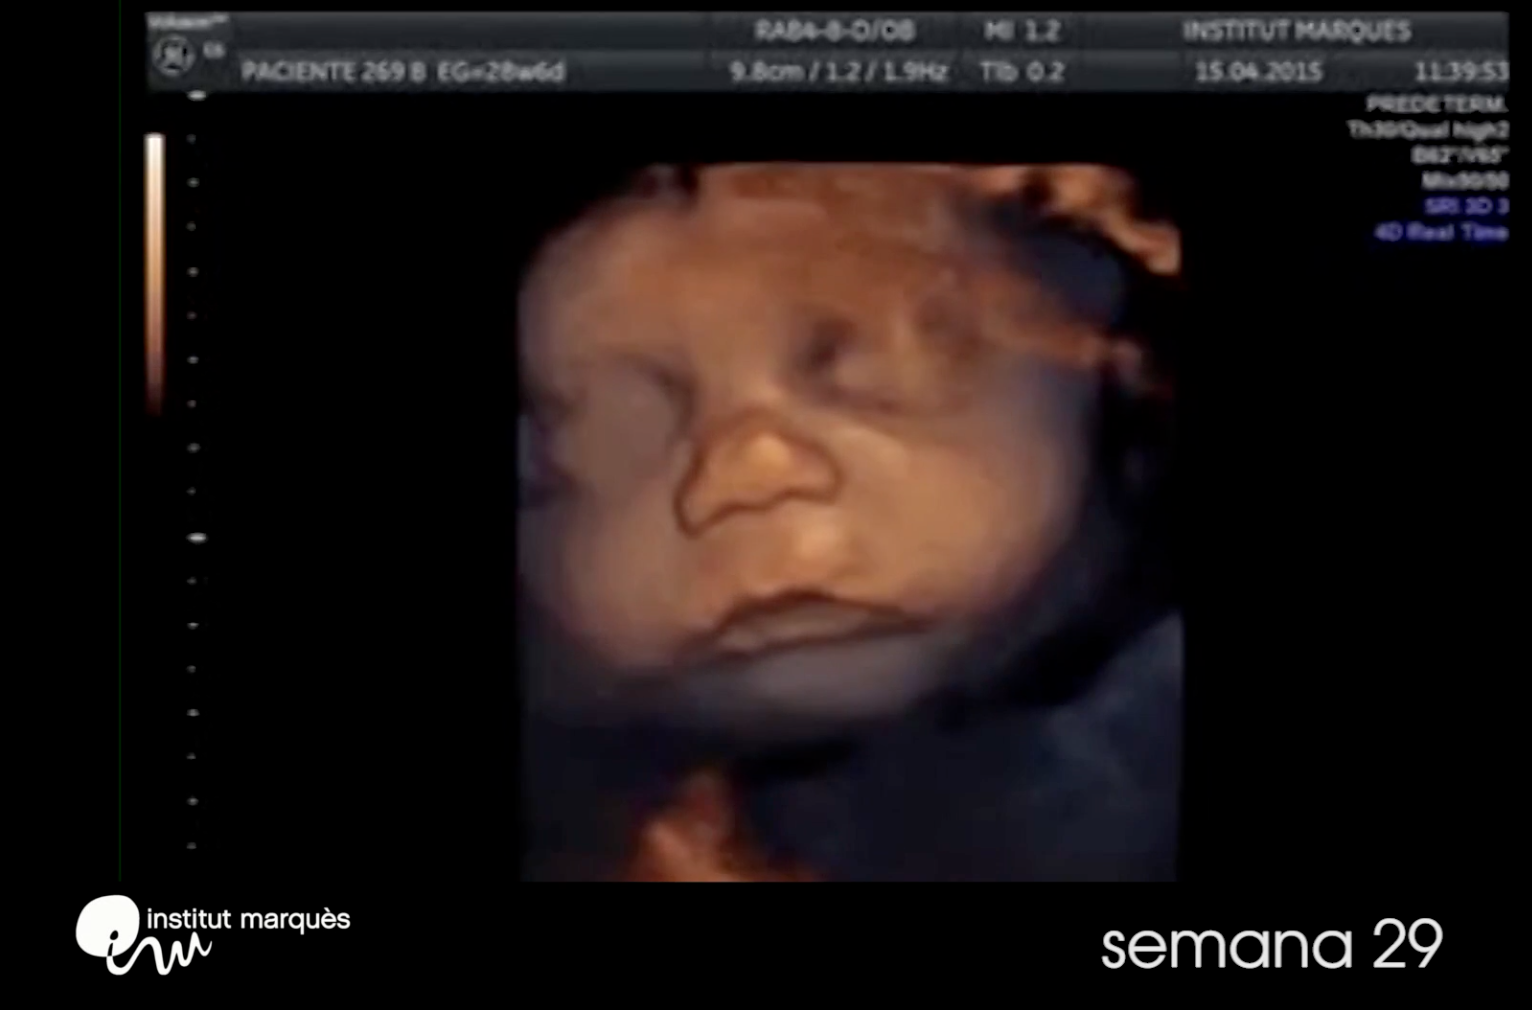

Around week 23 a fetus begins to experience REM sleep. With so few experiences to draw from, what can they be dreaming about?!

Fetuses in the womb can cry and produce tears!

This is possible because an unborn fetus has brain waves. Do you know when that develops?